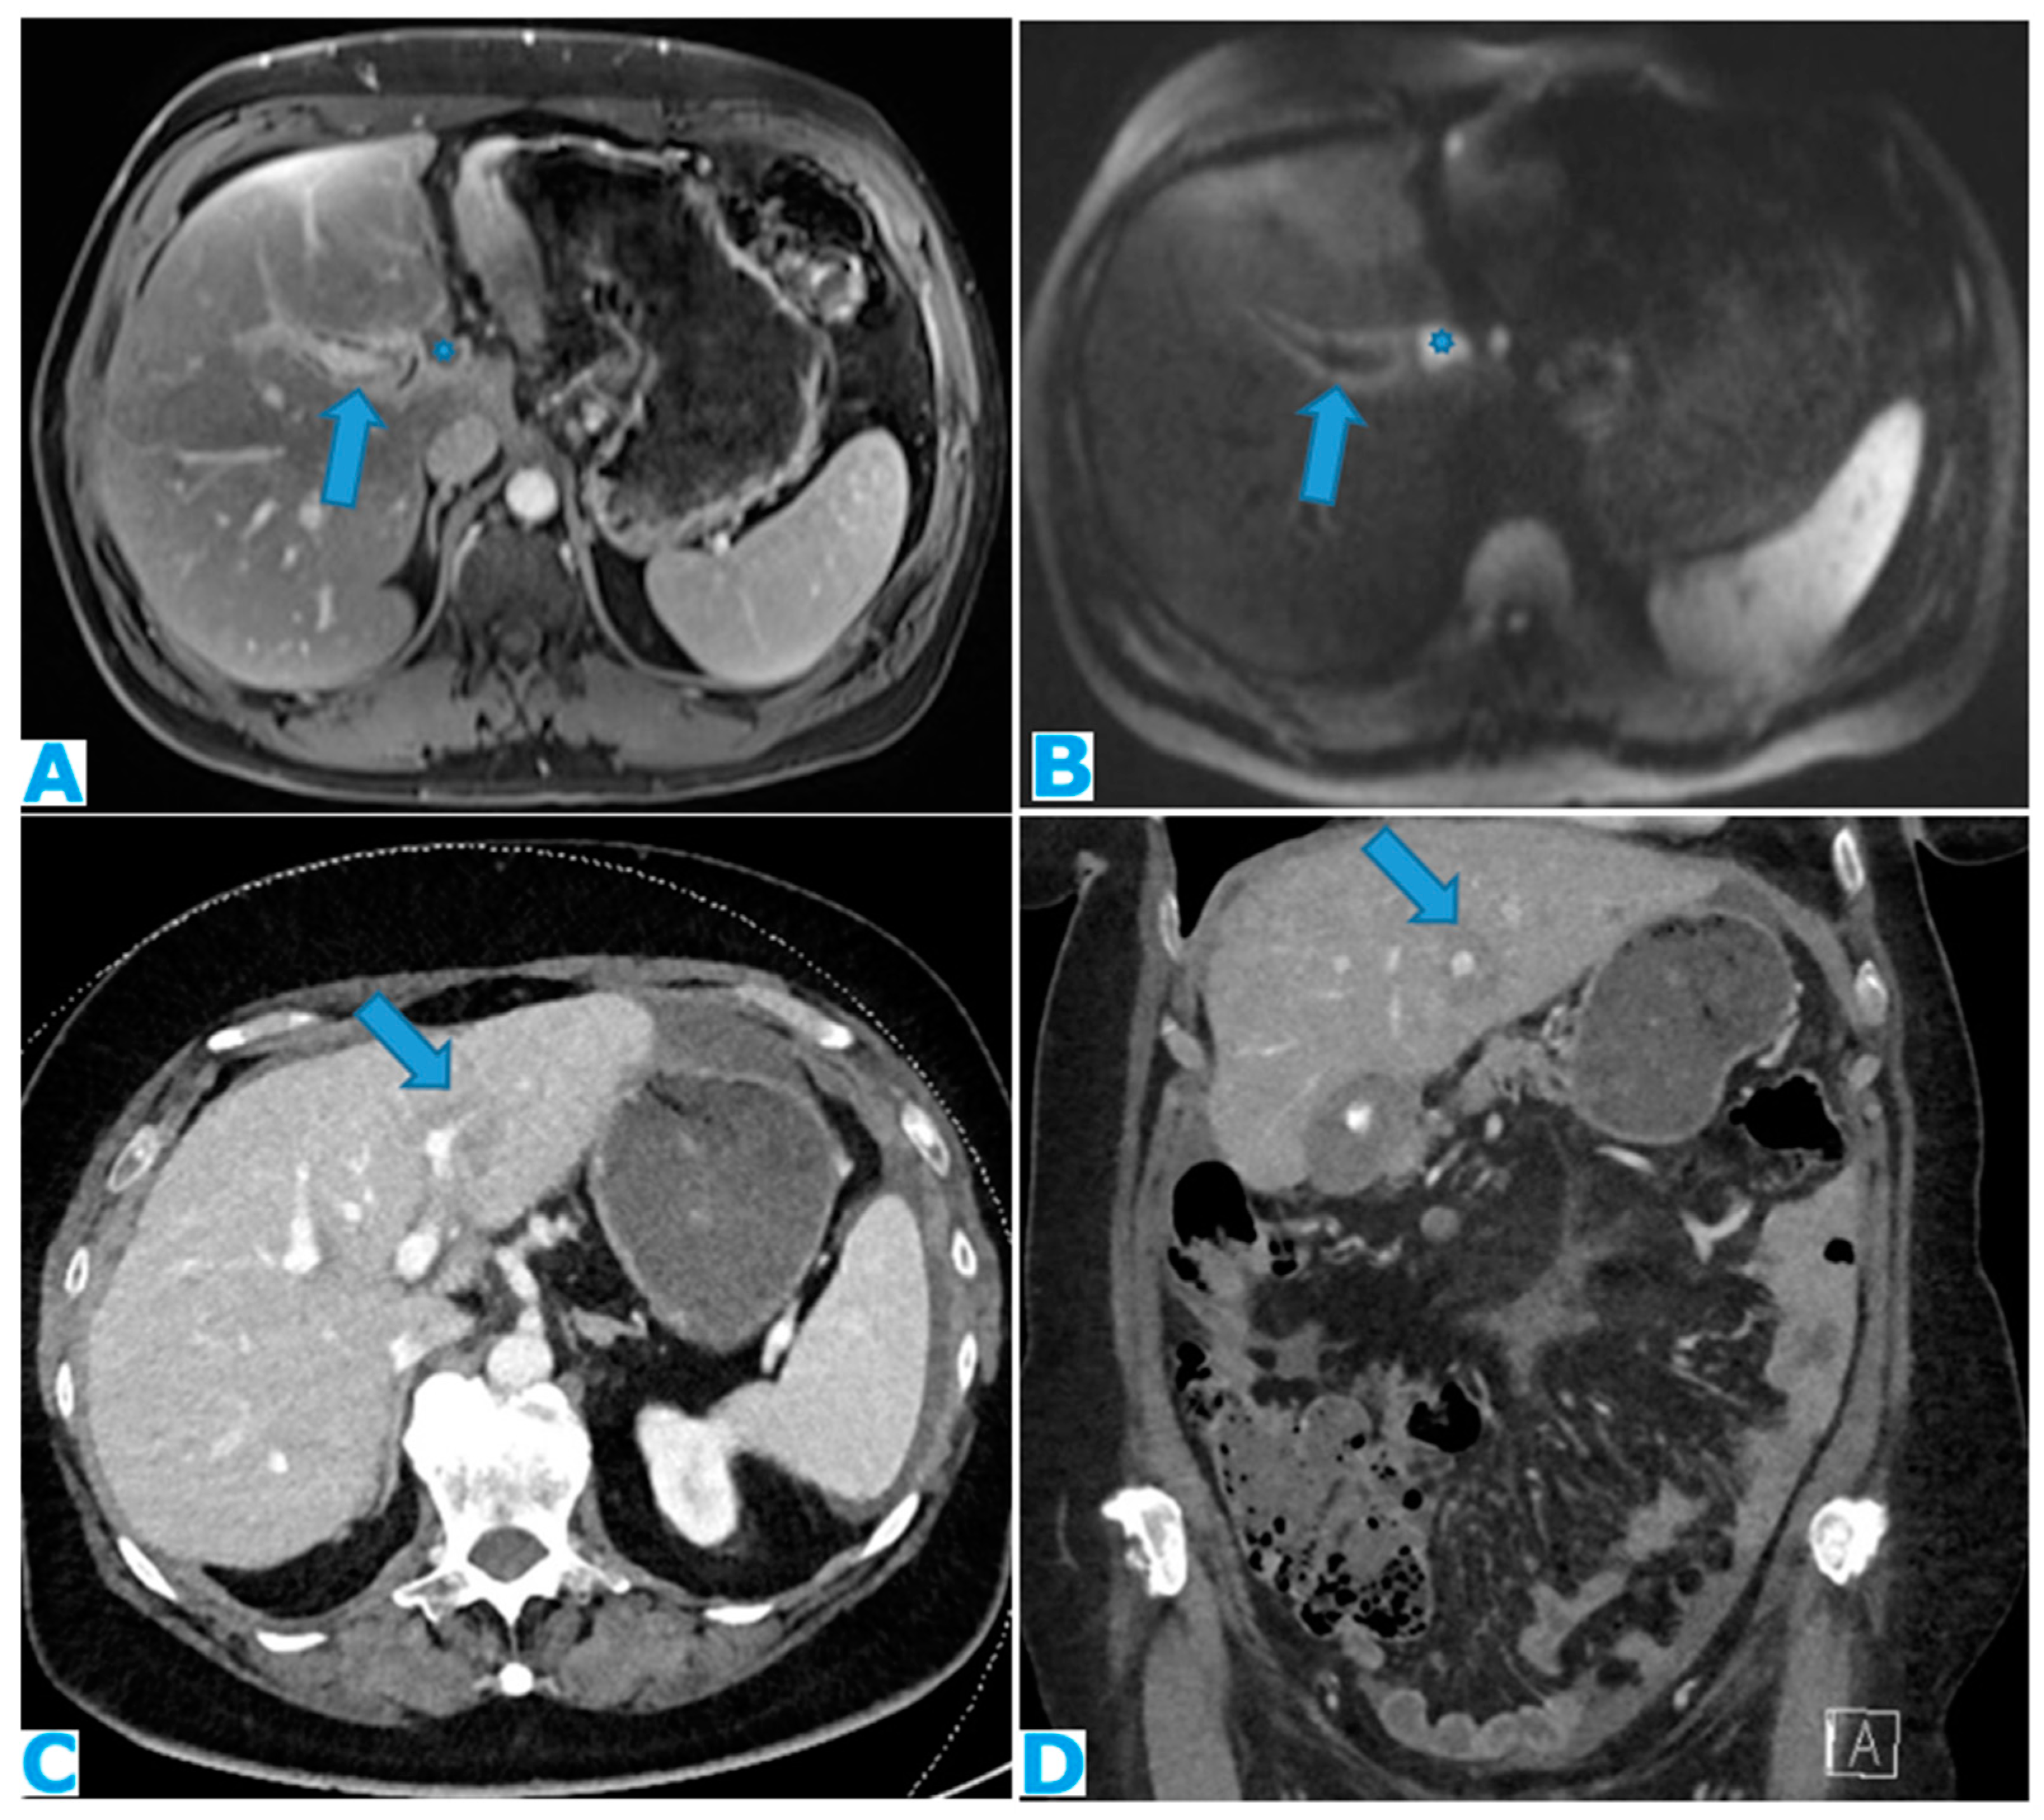

Figure 26.

Axial CE-CT (A). PC from stomach adenocarcinoma: Stellate mesentery. Axial CE portal phase FST1WI (B). PC from lobular breast adenocarcinoma: Stellate mesentery, notice the perivascular distribution. Axial CE-CT (C), axial T2WI (D). PC from stomach adenocarcinoma: Isolated perivascular deposit within the mesentery, as a soft tissue mass surrounding a branch of the SMV.